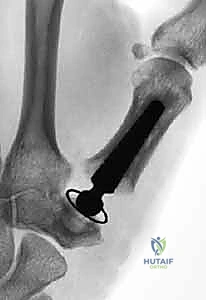

Page 40 of 47Thumb Carpometacarpal Joint Arthroplasty: An Intraoperative Masterclass in Resurfacing and Total Joint Replacement

- Mastering Silicone Arthroplasty for MCP and PIP Joints: An Intraoperative Guide

- Thumb Carpometacarpal Joint Ligament Stabilization: An Operative Masterclass

- Mastering Thumb CMC Resection Arthroplasty with FCR Suspensionplasty